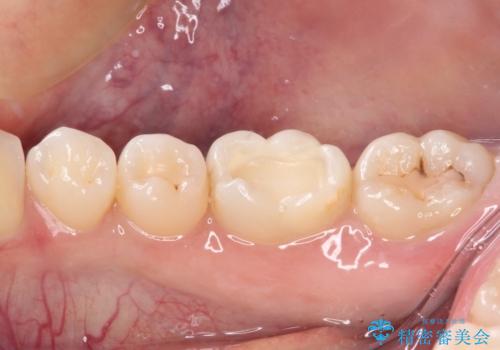

むし歯治療した歯にセラミックを入れたい セラミックインレー修復

- 他院にてむし歯の治療をし、当院にてセラミックを入れたいとのことで来院された患者様です。

むし歯がないか確認し、セラミックインレーにて修復することとしました。

セラミックインレー装着時には、唾液の侵入を防ぐために、ラバーダム防湿を行いました。